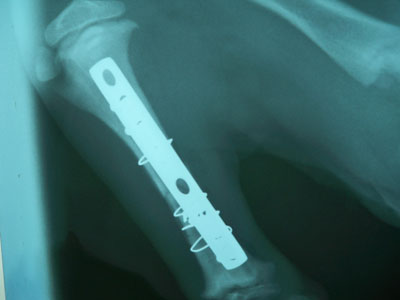

Μετά την ανάταξη του κατάγματος και την συγκράτηση του απολλύματος με μεταλλικό ράμμα τοποθετήθηκε στην έσω επιφάνεια της κνήμης μεταλλική πλάκα 2,7mm και 3 κοχλίες 2,7 mm στο κεντρικό τμήμα και 3 κοχλίες 2,7 mm στο περιφερικό.Κατά την διάρκεια του χειρουργείου διαπιστώθηκε ο,τι κλώτσησαν 4 από τους κοχλίες. 3 περιφερικά και γι΄ αυτό τοποθετήθηκαν δύο μεταλλικά ράμματα και 1 κοχλίας κεντρικά και τοποθετήθηκε 1 μεταλλικό ράμμα.

Μετεγχειρητικά χορηγήθηκε VIFAZOLIN 1,5ml BID και DALACIN 0,3ml BID για 2-3 ημέρες. Και στη συνέχεια χορηγήθηκε CLINDAVET 75mg 1 χάπι BID για 7 ημέρες και 0,5ml CONVENIA.Η αποκάτασταση ήταν 100% και τα υλικά αφαιρέθηκαν 3 μήνες μετά .